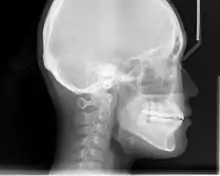

Cephalometric radiographs

Cephalometric analysis depends on cephalometric radiography to study relationships between bony and soft tissue landmarks and can be used to diagnose facial growth abnormalities prior to treatment, in the middle of treatment to evaluate progress, or at the conclusion of treatment to ascertain that the goals of treatment have been met.[5] A Cephalometric radiograph is a radiograph of the head taken in a Cephalometer (Cephalostat) that is a head-holding device introduced in 1931 by Holly Broadbent Sr. in USA.[6] The Cephalometer is used to obtain standardized and comparable craniofacial images on radiographic films.

Lateral cephalometric radiographs

Lateral cephalometric radiograph is a radiograph of the head taken with the x-ray beam perpendicular to the patient's sagittal plane. Natural head position is a standardized orientation of the head that is reproducible for each individual and is used as a means of standardization during analysis of dentofacial morphology both for photos and radiographs. The concept of natural head position was introduced by Coenraad Moorrees and M. R Kean in 1958[9][10] and now is a common method of head orientation for cephalometric radiography.[11][12]